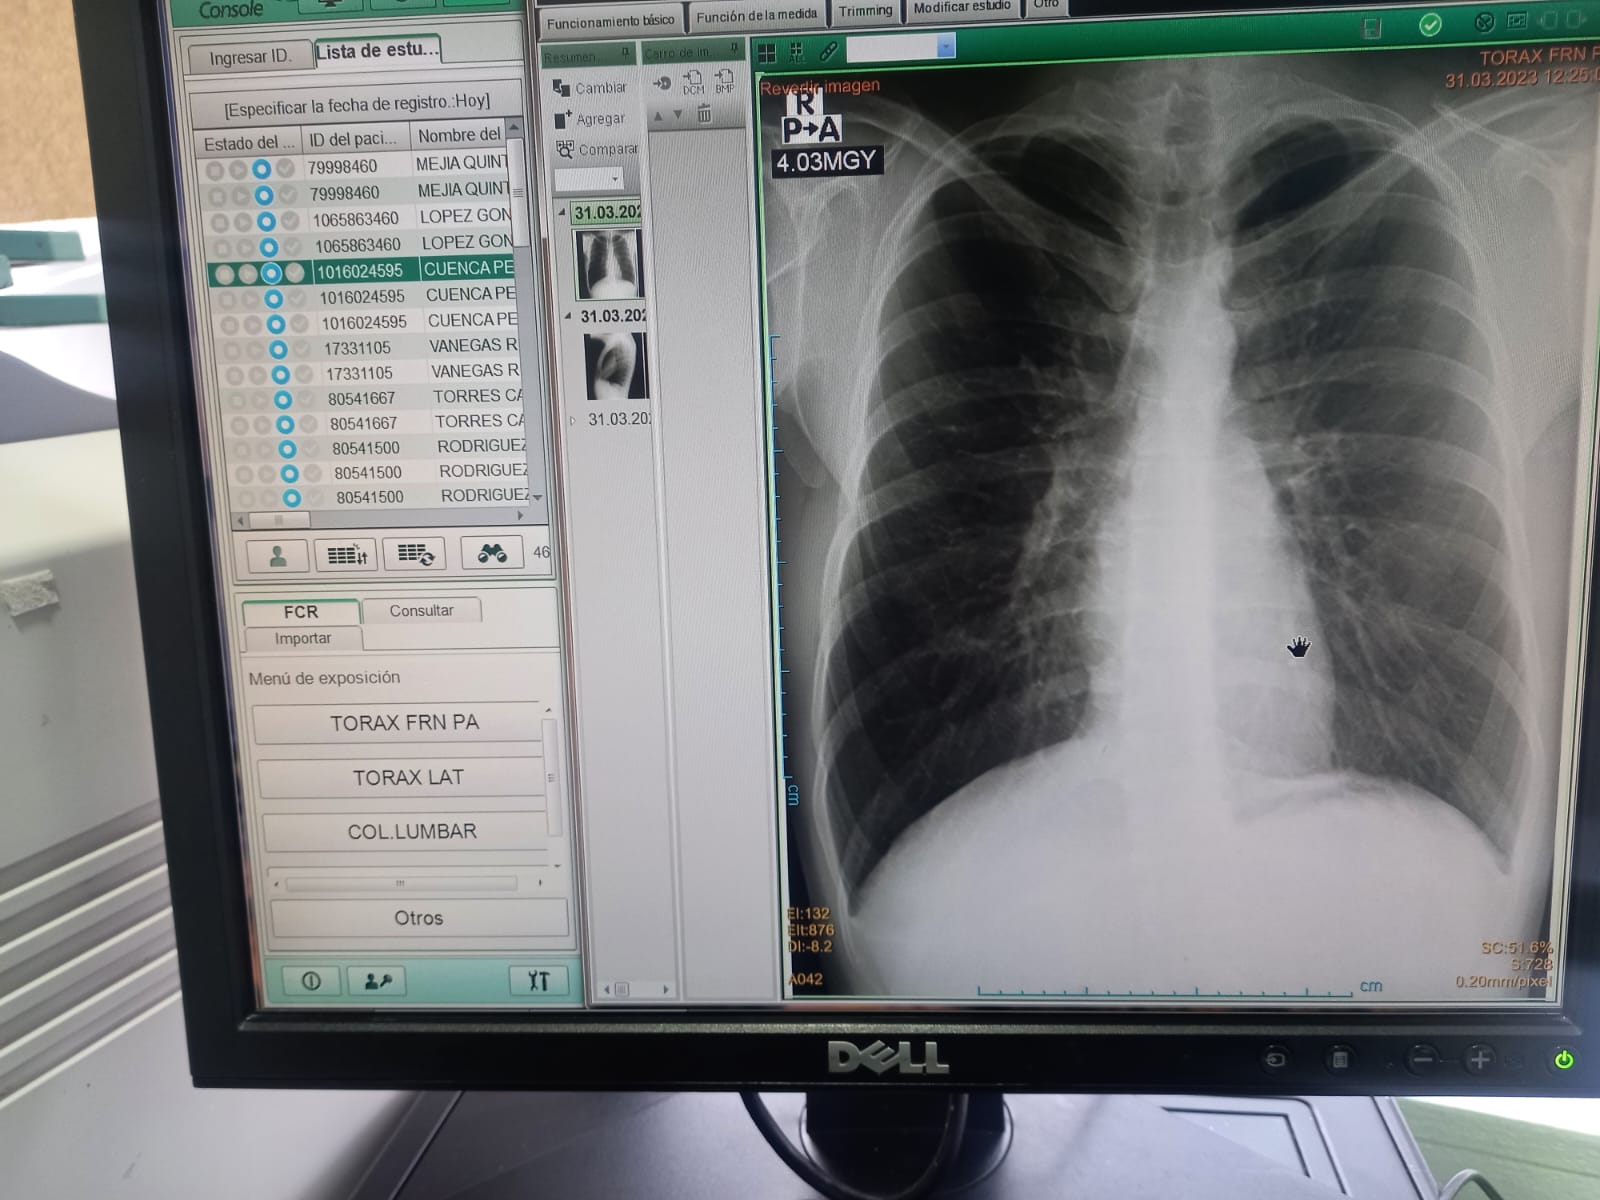

Rayos X (digital)

Equipo de Radiología

Radiografía de tórax con lectura internacional ILO

La clasificación ILO (Organización Internacional del Trabajo) se utiliza principalmente para evaluar las radiografías de tórax de los trabajadores que han estado expuestos a riesgos ocupacionales relacionados con enfermedades respiratorias, como la silicosis y el asbestosis.

La interpretación de las radiografías se lleva a cabo por un radiólogo capacitado que utiliza criterios OIT y NIOSH (National Institute for Occupational Safety and Health) lector B para evaluar la presencia y la gravedad de las anomalías pulmonares. Esta proporciona una evaluación objetiva y estandarizada de las radiografías de tórax, lo que ayuda a mejorar la calidad y la precisión de la interpretación radiológica. En Colombia hay pocas profesionales con esta certificación.